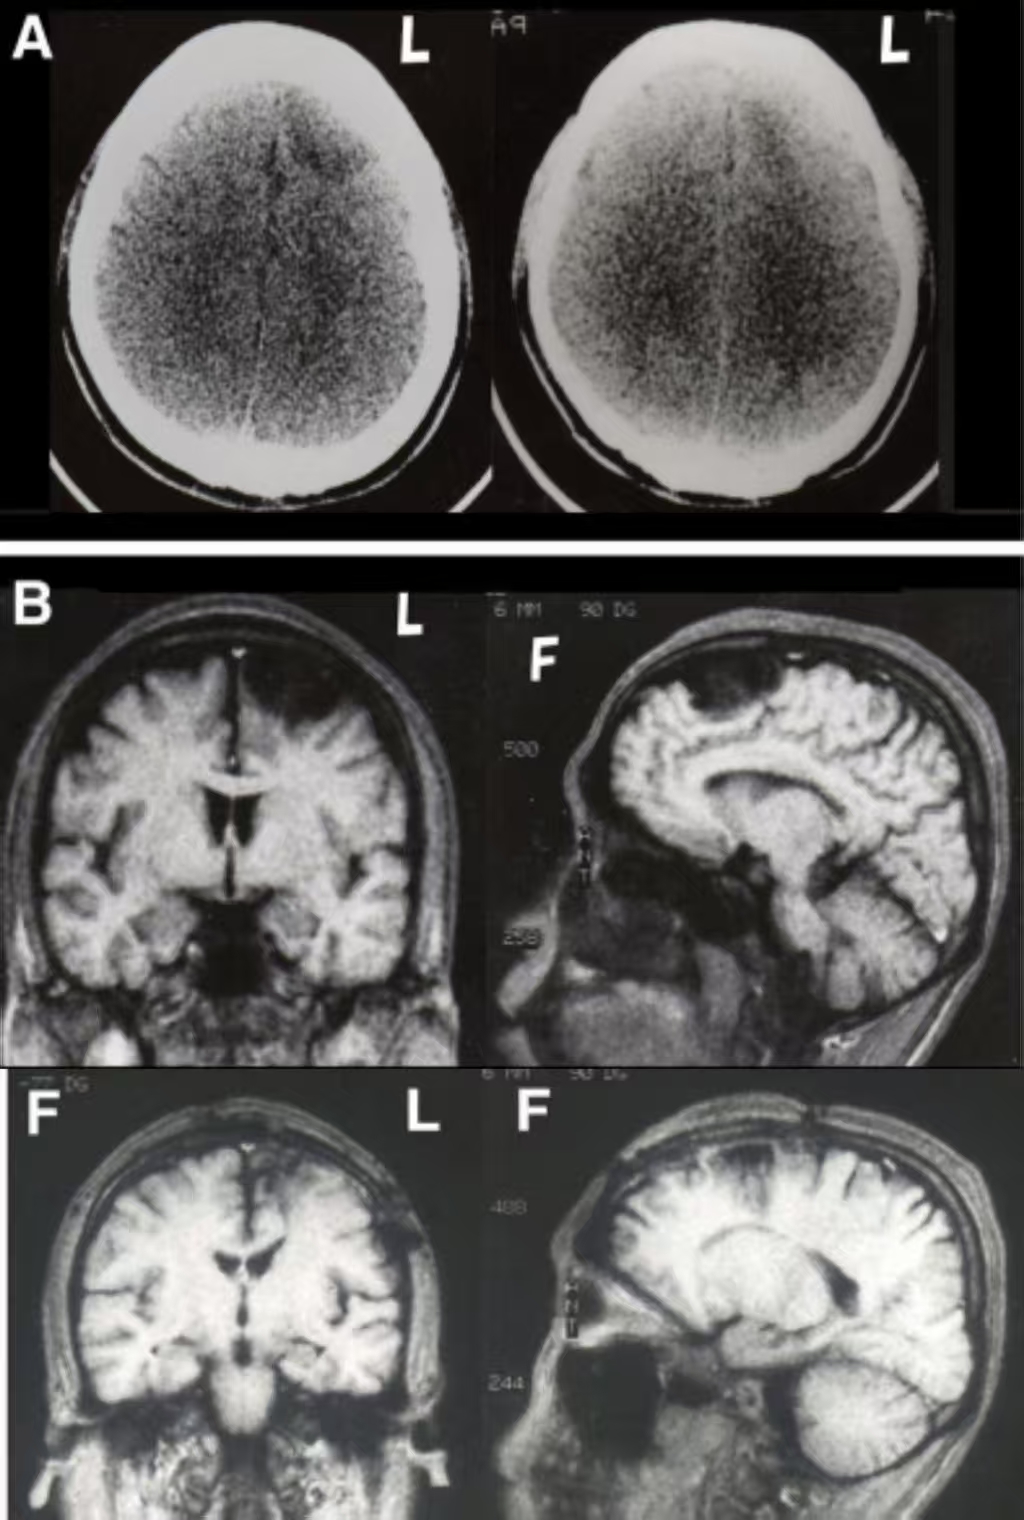

质子治疗是一种放射疗法。在常规的放射治疗中,使用的是被称为光子线的电磁波,如X射线和伽马射线来进行治疗;而在质子线治疗中,则使用一种称为质子线的放射线来进行治疗。

在癌症治疗中,放射治疗是一把双刃剑,这种治疗方式在杀灭癌细胞的同时难免伤及健康组织。而质子治疗的出现,为癌症患者带来了精准治疗选择。

质子疗法与传统放射治疗中使用的 X 射线不同,它利用质子束精确靶向癌细胞。质子直接在肿瘤内的特定深度(称为布拉格峰)释放大部分能量。传统放疗的X射线是一种能量射线,它们进入人体后从另一侧穿出。由于在进入人体时释放的辐射最强,它们可能在抵达肿瘤的路径上损伤健康组织和器官。当这些射线继续穿过人体、经过肿瘤后,也可能对健康组...

质子治疗是当今先进的放射治疗形式之一,能够将高剂量的辐射直接作用于肿瘤,同时保护周围的健康组织。它通过利用布拉格峰发挥作用,在组织的预定深度释放大部分质子能量。这与传统的基于光子的放射治疗形成了鲜明对比,在光子治疗中,辐射会沿着整个射线路径持续释放,不仅损伤癌细胞,也会损害周围的健康细胞。质子可以被控制在特定点(布拉格...